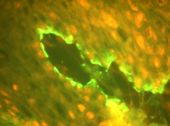

La Inmunofluorescencia Directa (IFD) realizada en la Cátedra de Dermatología del Hospital de Clínicas mostró: Ig. G depósito lineal altamente positivo en la membrana basal del epitelio (Fotos 6 – 7). Ig A: depósito en la capa basal. (Foto 8). C3: presente en la capa basal.

Foto 6 Foto 6 IFD: presencia lineal de IgG

Foto 7. IFD: Presencia lineal de IgA

Foto 8 IFD: positividad lineal para C3

La IFD realizada en la Cátedra de Dermatología del Hospital de Clínicas demostró: depósitos lineales en membrana basal de Ig G (Fotos 11 y 12), Ig A (foto 13) y C3.

Foto 11 IFD: presencia lineal IgG

Foto 12 IFD: presencia lineal IgA

Foto 13 IFD: presencia lineal C3

Como quedara establecido en el Primer Consenso Internacional de PMM, la inmunofluorescencia es de rigor para el diagnóstico definitivo de PMM. Los estudios de inmunoflurescencia directa (IFD) muestran un patrón de fijación lineal altamente positivo para Ig G y C3. Las Ig M e Ig A pueden observarse junto o en lugar de la Ig G.

La segunda técnica de inmunodiagnóstico empleada es la Inmunofluorescencia Indirecta (IFI); constituye el estudio de anticuerpos antimembrana basal circulantes en suero del paciente y se estudian la Ig G y Ig A. Pero no todos los pacientes con PMM poseen autoanticuerpos circulantes en el suero, por lo que este estudio no constituye un criterio absoluto para el diagnóstico. Su positividad está vinculada con la extensión de la enfermedad, con la fase activa o de reposo y con el tipo de sustrato utilizado en la técnica (7).